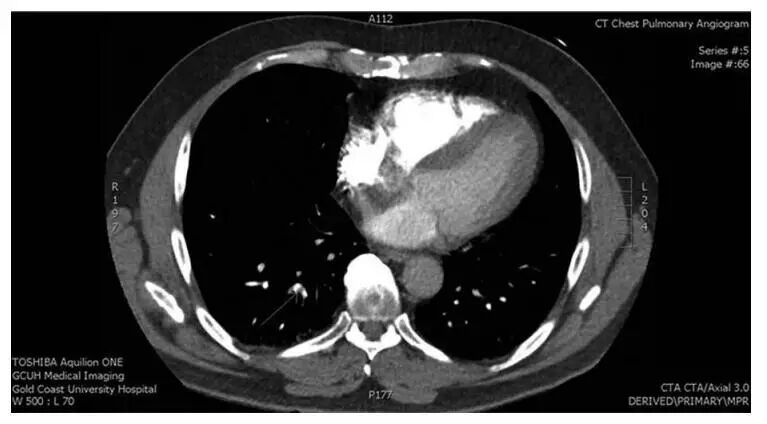

于急诊完善心电图提示完全性右束支传导阻滞,胸片大致正常,TNI回报0.017ng/ml(参考值<0.04ng/ml),考虑患者肺栓塞临床可能性低,未再进一步行D-D及肺栓塞CT检查。1周后患者再次因胸痛于急诊就诊,性质同前,查TNI 0.011ng/ml,D-dimer 290ng/ml(免疫比浊法),因患者胸痛原因未能明确,连续心电图及心肌酶变化除外心源性原因,行肺栓塞CT检查明确有无肺栓塞可能,发现右肺亚段肺动脉栓塞(图2)。

图2 肺栓塞CT扫描明确右肺亚段水平肺栓塞